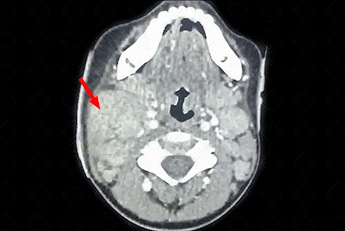

Texto alternativo para a imagem Figura 2. Créditos: Dra. Elazir Mota - Rio de Janeiro/RJ

Descrição da figura 2: Tomografia computadorizada do pescoço após administração do meio de contraste evidenciando glândula parótida direita com dimensões muito aumentadas e com hiper-realce pós-contraste (seta vermelha).

• T omografia computadorizada do pescoço: D eve ser realizada somente diante da suspeita de complicações, como presença de abscessos. Também observaremos após a administração do contraste uma glândula com sua atenuação e volume aumentados, difusamente heterogênea, podendo conter pequenas coleções no seu interior. Aqui vale a ressalva de realizar o estudo do pescoço sempre com o uso de contraste venoso (f igura 2) ;